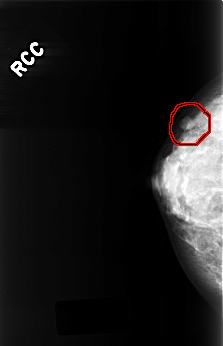

C_0336_1.RIGHT_CC

RIGHT_CC LINES 4488 PIXELS_PER_LINE 2888 BITS_PER_PIXEL 12 RESOLUTION 50 OVERLAY

FILE: C_0336_1.RIGHT_CC.OVERLAY

TOTAL_ABNORMALITIES 1

ABNORMALITY 1

LESION_TYPE MASS SHAPE OVAL MARGINS CIRCUMSCRIBED

ASSESSMENT 4

SUBTLETY 5

PATHOLOGY BENIGN

TOTAL_OUTLINES 1

BOUNDARY